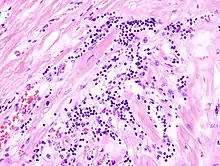

Acute myocardial infarction

Der Myokardinfarkt muss mind. 6 - 12 Stunden überlebt werden, bevor er morphologisch sichtbar wird!

Mikro: Koagulationsnekrose, Einblutungen. Die Myozyten zeigen eine verstärkte Eosinophilie und Kontraktionsbanden quer durch die Herzmuskelfasern. Typische Zellparameter wie Querstreifung, Zellkerne und Zellgrenzen gehen verloren. Das Infarktareal wird von einer Hyperämischen/hämorrhagischen Randzone begrenzt. Im Verlauf zunehmende leukozytäre Demarkation und Phagozytose des nekrotischen Gewebes, sowie Einwanderung von Fibroblasten mit Ausbildung eines narbigen Ersatzgewebes.

![]() Akuter Myokardinfarkt, H&E. |